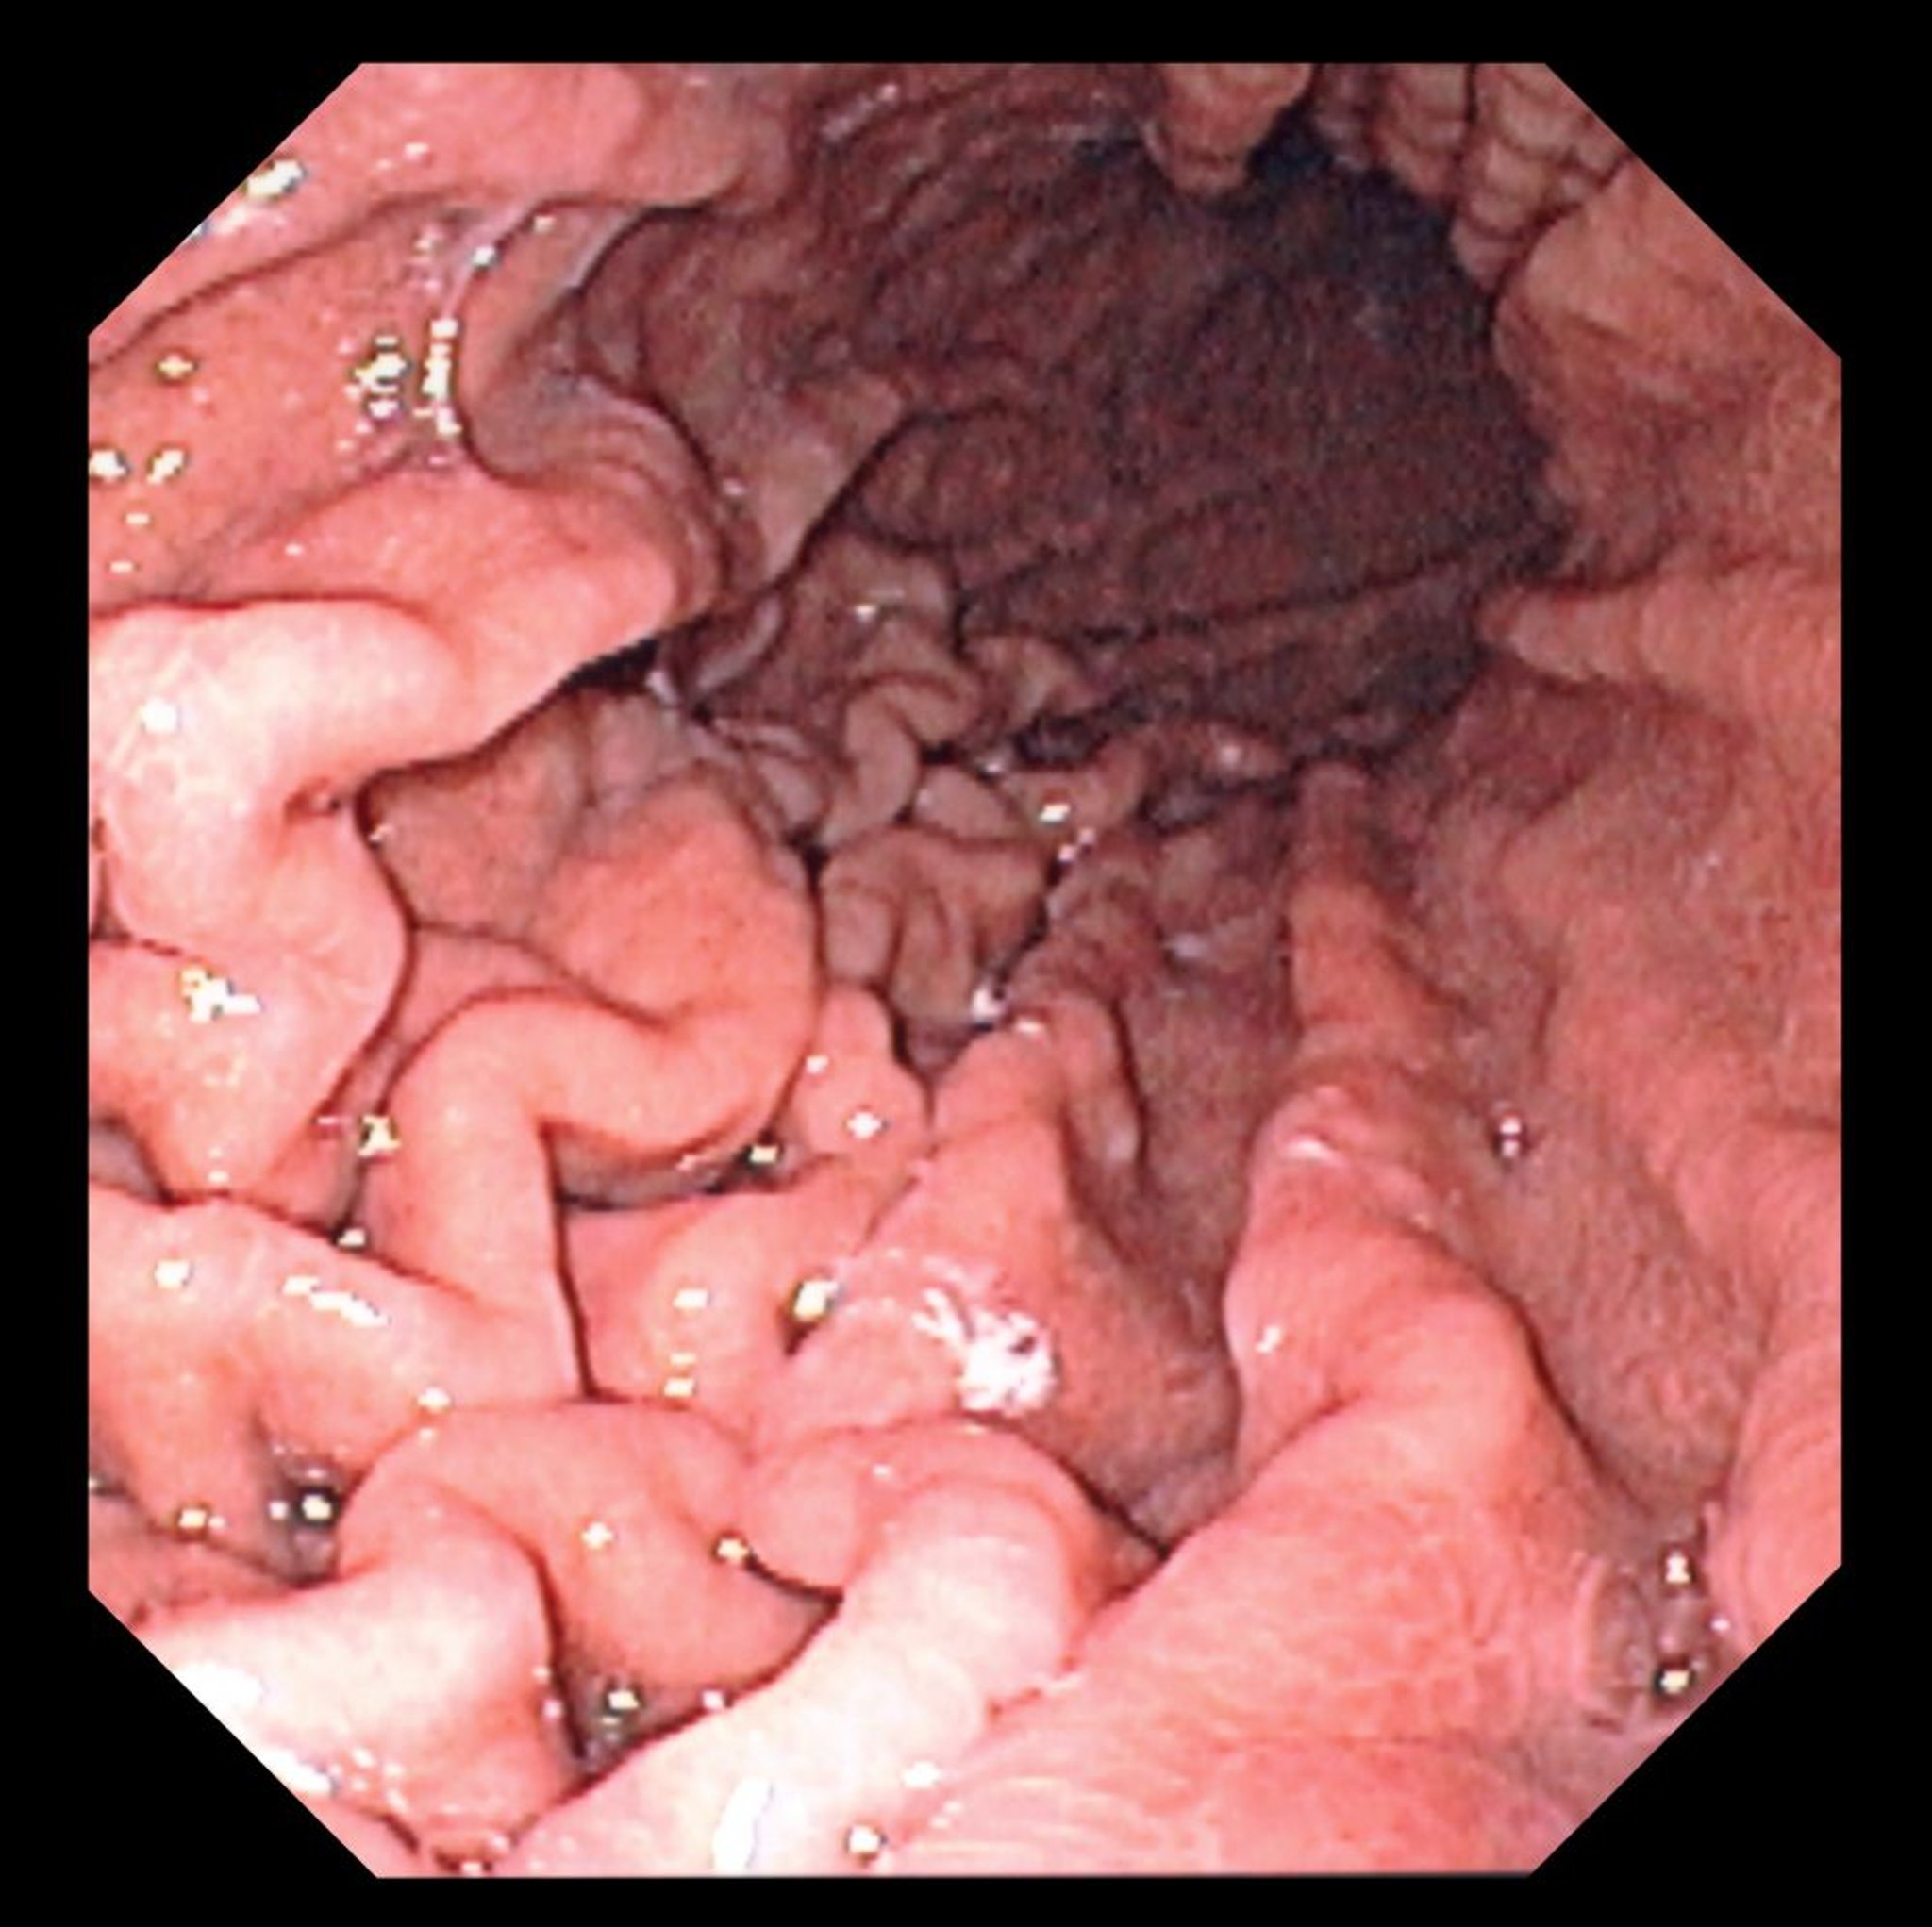

内視鏡検査(胃)

この写真には,特徴的な胃皺襞を認める正常な胃底部の内視鏡像が写っている。

DAVID M.MARTIN, MD/SCIENCE PHOTO LIBRARY